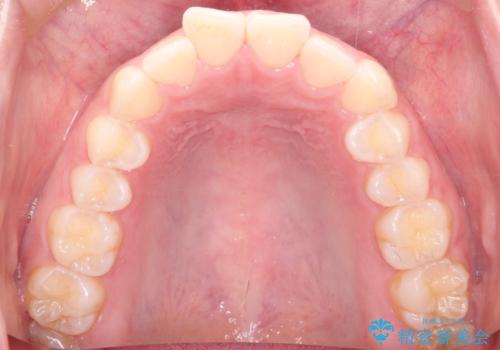

【インビザライン】前歯が出ているのを治したい

- 前歯が出ていることを主訴に来院されました。

前歯の突出感が改善され、満足していただきました。